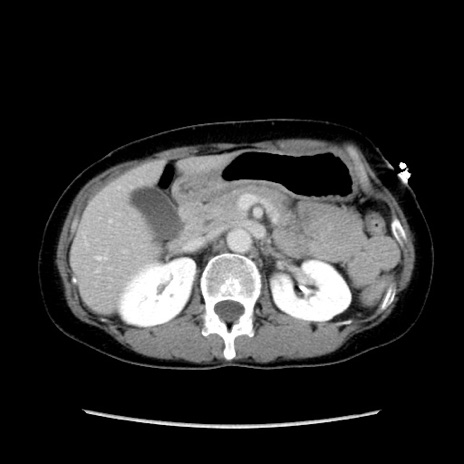

冠状断像

【症例】40歳代 女性

【主訴】上腹部痛、嘔気・嘔吐

【現病歴】約9時間前頃から急に上腹部痛、嘔気、嘔吐が出現。改善しないため救急要請。

【既往歴】子宮頚癌(広汎子宮全摘術、放射線療法)、腸閉塞

【身体所見】腹部:平坦、軟、腸雑音亢進、上腹部を中心に腹部全体に圧痛あり。

【データ】WBC 8400、CRP 0.03